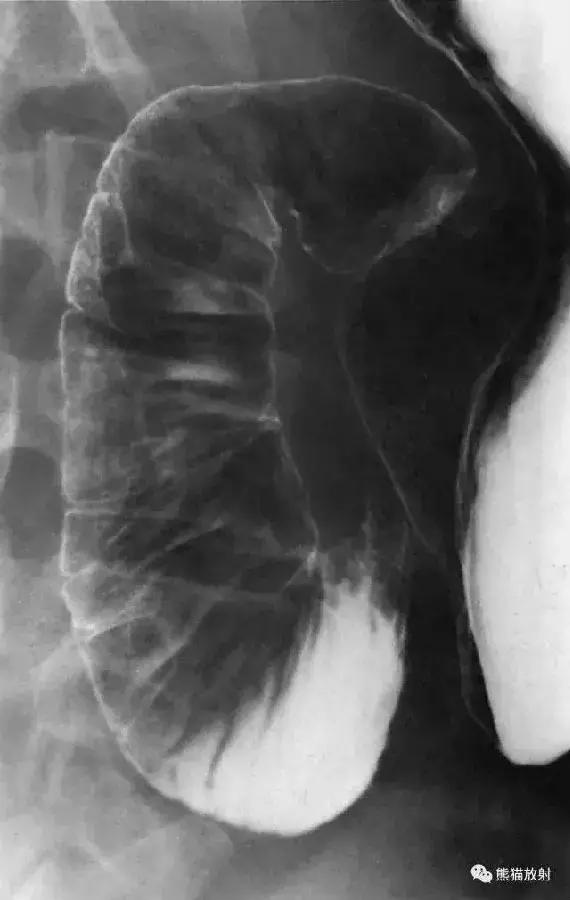

九、回盲部(点片)

图17 回盲部(点片)

图18 回盲部解剖示意图。1 结肠袋,2 升结肠,3 回肠,4 回盲瓣,5 末端回肠,6 盲肠